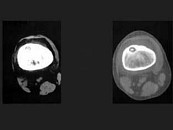

- 单项选择题男,36岁, 左大腿疼痛,夜间疼痛加剧, 结合所提供的图像,最可能的诊断是 ( )

A、良性骨母细胞瘤

B、骨样骨瘤

C、骨纤维异常增殖症

D、纤维性骨皮质缺损

E、非骨化性骨纤维瘤